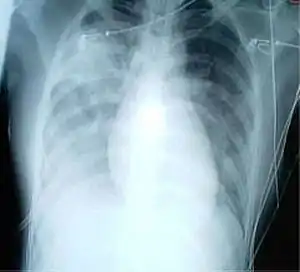

Une radiographie pulmonaire montrant des opacités dans les deux poumons, indicatives d'une pneumonie, chez un patient atteint de SRAS.

Courant , les autorités locales chinoises tentent de réduire au silence le personnel médical qui constate un nombre de plus en plus important de patients avec des cas présentant des symptômes similaires au syndrome respiratoire aigu sévère (SRAS)[169]. Ai Fen, cheffe des urgences de l’hôpital central de Wuhan, est la première à diffuser l’information auprès de collègues pour les mettre en garde et leur conseiller de se protéger[169]. Parmi eux, le docteur Li Wenliang, qui décédera par la suite de la Covid-19, diffuse à un groupe d’amis une photo des résultats de test d’un patient transmise par Ai Fen, où elle avait entouré de rouge les mots « coronavirus Sras »[169]. Il fait partie des huit médecins convoqués par la suite et sermonnés par la police pour diffusion de rumeurs[169]. Ai Fen reçoit l'ordre de ses supérieurs de ne plus communiquer[169].